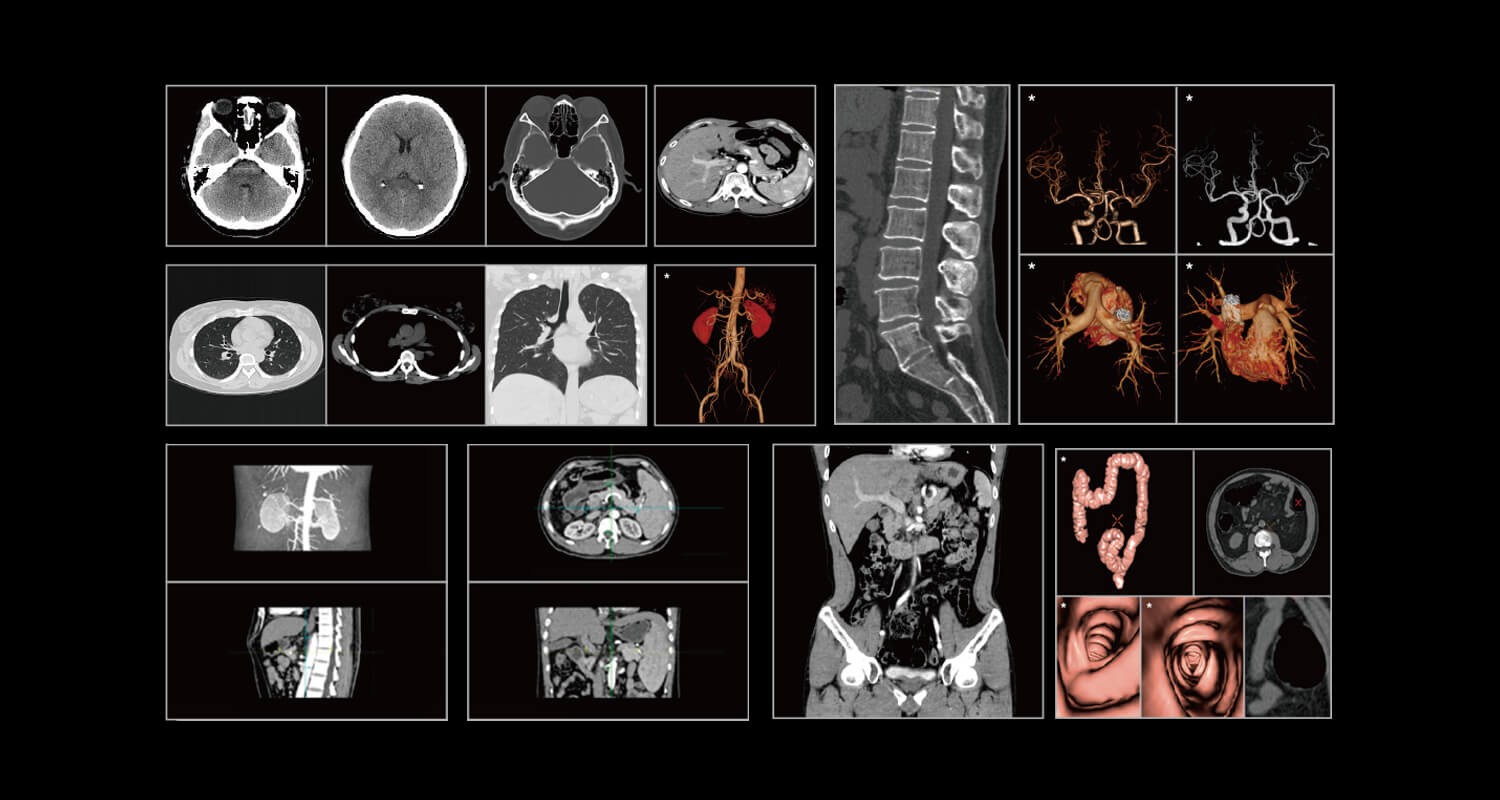

臨床畫廊